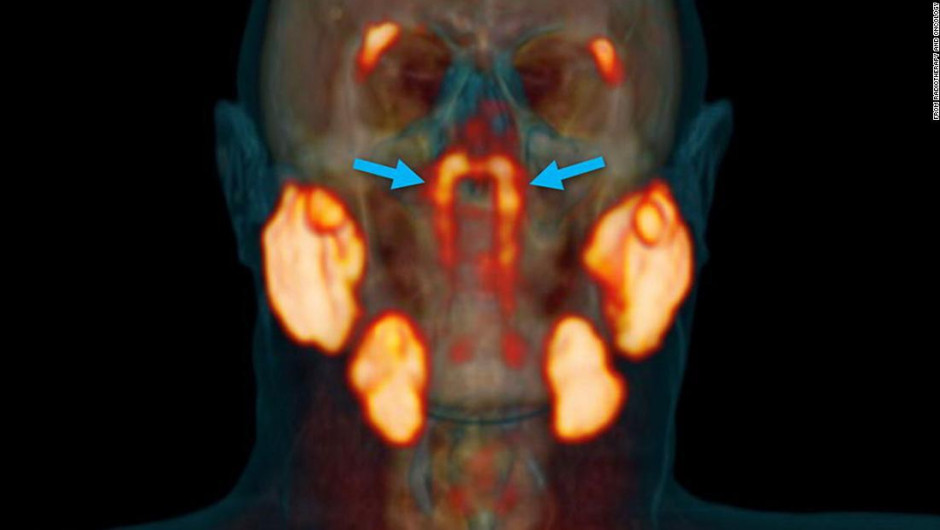

La «entidad desconocida» solo se identificó cuando los médicos utilizaban un tipo de exploración nuevo y avanzado llamado PSMA PET/CT que se ha utilizado para detectar la propagación del cáncer de próstata. PSMA PET es la abreviatura de la obtención de imágenes de antígeno de membrana específico de la próstata mediante tomografía por emisión de positrones.

Vista de los tejidos de glándulas salivales escaneados por PSMA PET/CT.

Dijeron que han descubierto un par de glándulas previamente pasadas por alto que están escondidas en nuestros cráneos donde se encuentran la cavidad nasal y la garganta.

Los investigadores médicos encontraron por primera vez la parte del cuerpo, que proponen nombrar glándulas tubarias, durante una exploración diseñada para buscar crecimientos tumorales.